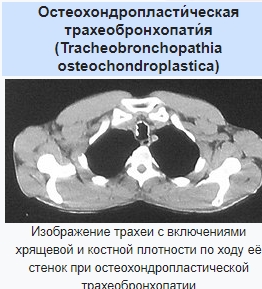

В эндоскопическом атласе обычно представлены изображения и видео, полученные во время процедур, проводимых врачами-эндоскопистами. Эти изображения и видео могут использоваться для обучения студентов медицинских учебных заведений, повышения квалификации медицинских работников, а также для консультации врачей при диагностике и лечении различных заболеваний.